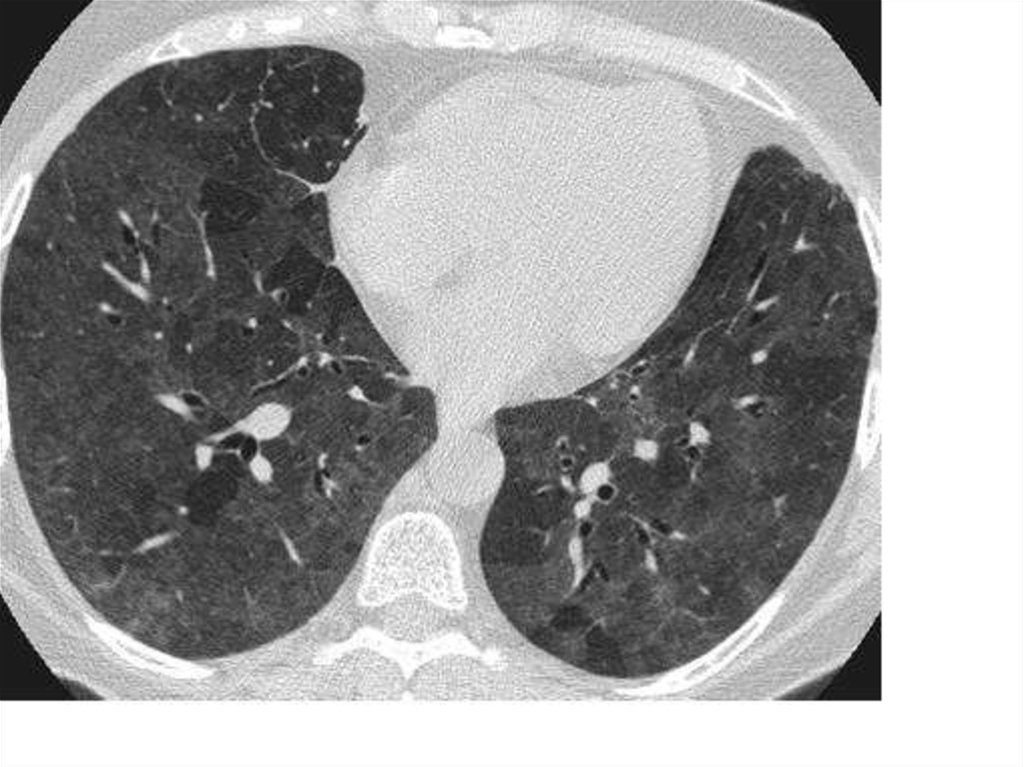

10. Диагностика

11. Диагностика